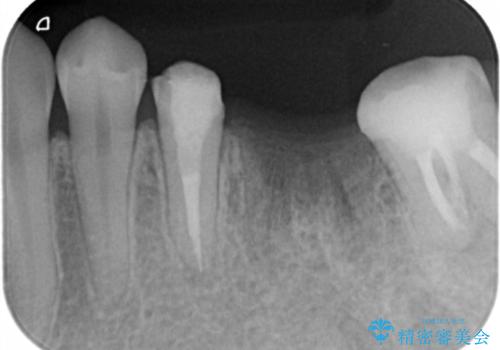

虫歯を放置したため、左下奥歯の上下の歯の隙間が全くなく入れ歯もインプラントも難しい状態でした。

左下6番は残根状態だったため、やむなく抜歯を行い、⑤6⑦ブリッジとしました。

左下7番(一番奥)の歯の根管治療は横浜桜木町歯科院長大元が担当しています。

左下5番の根管治療は井上が担当しました。